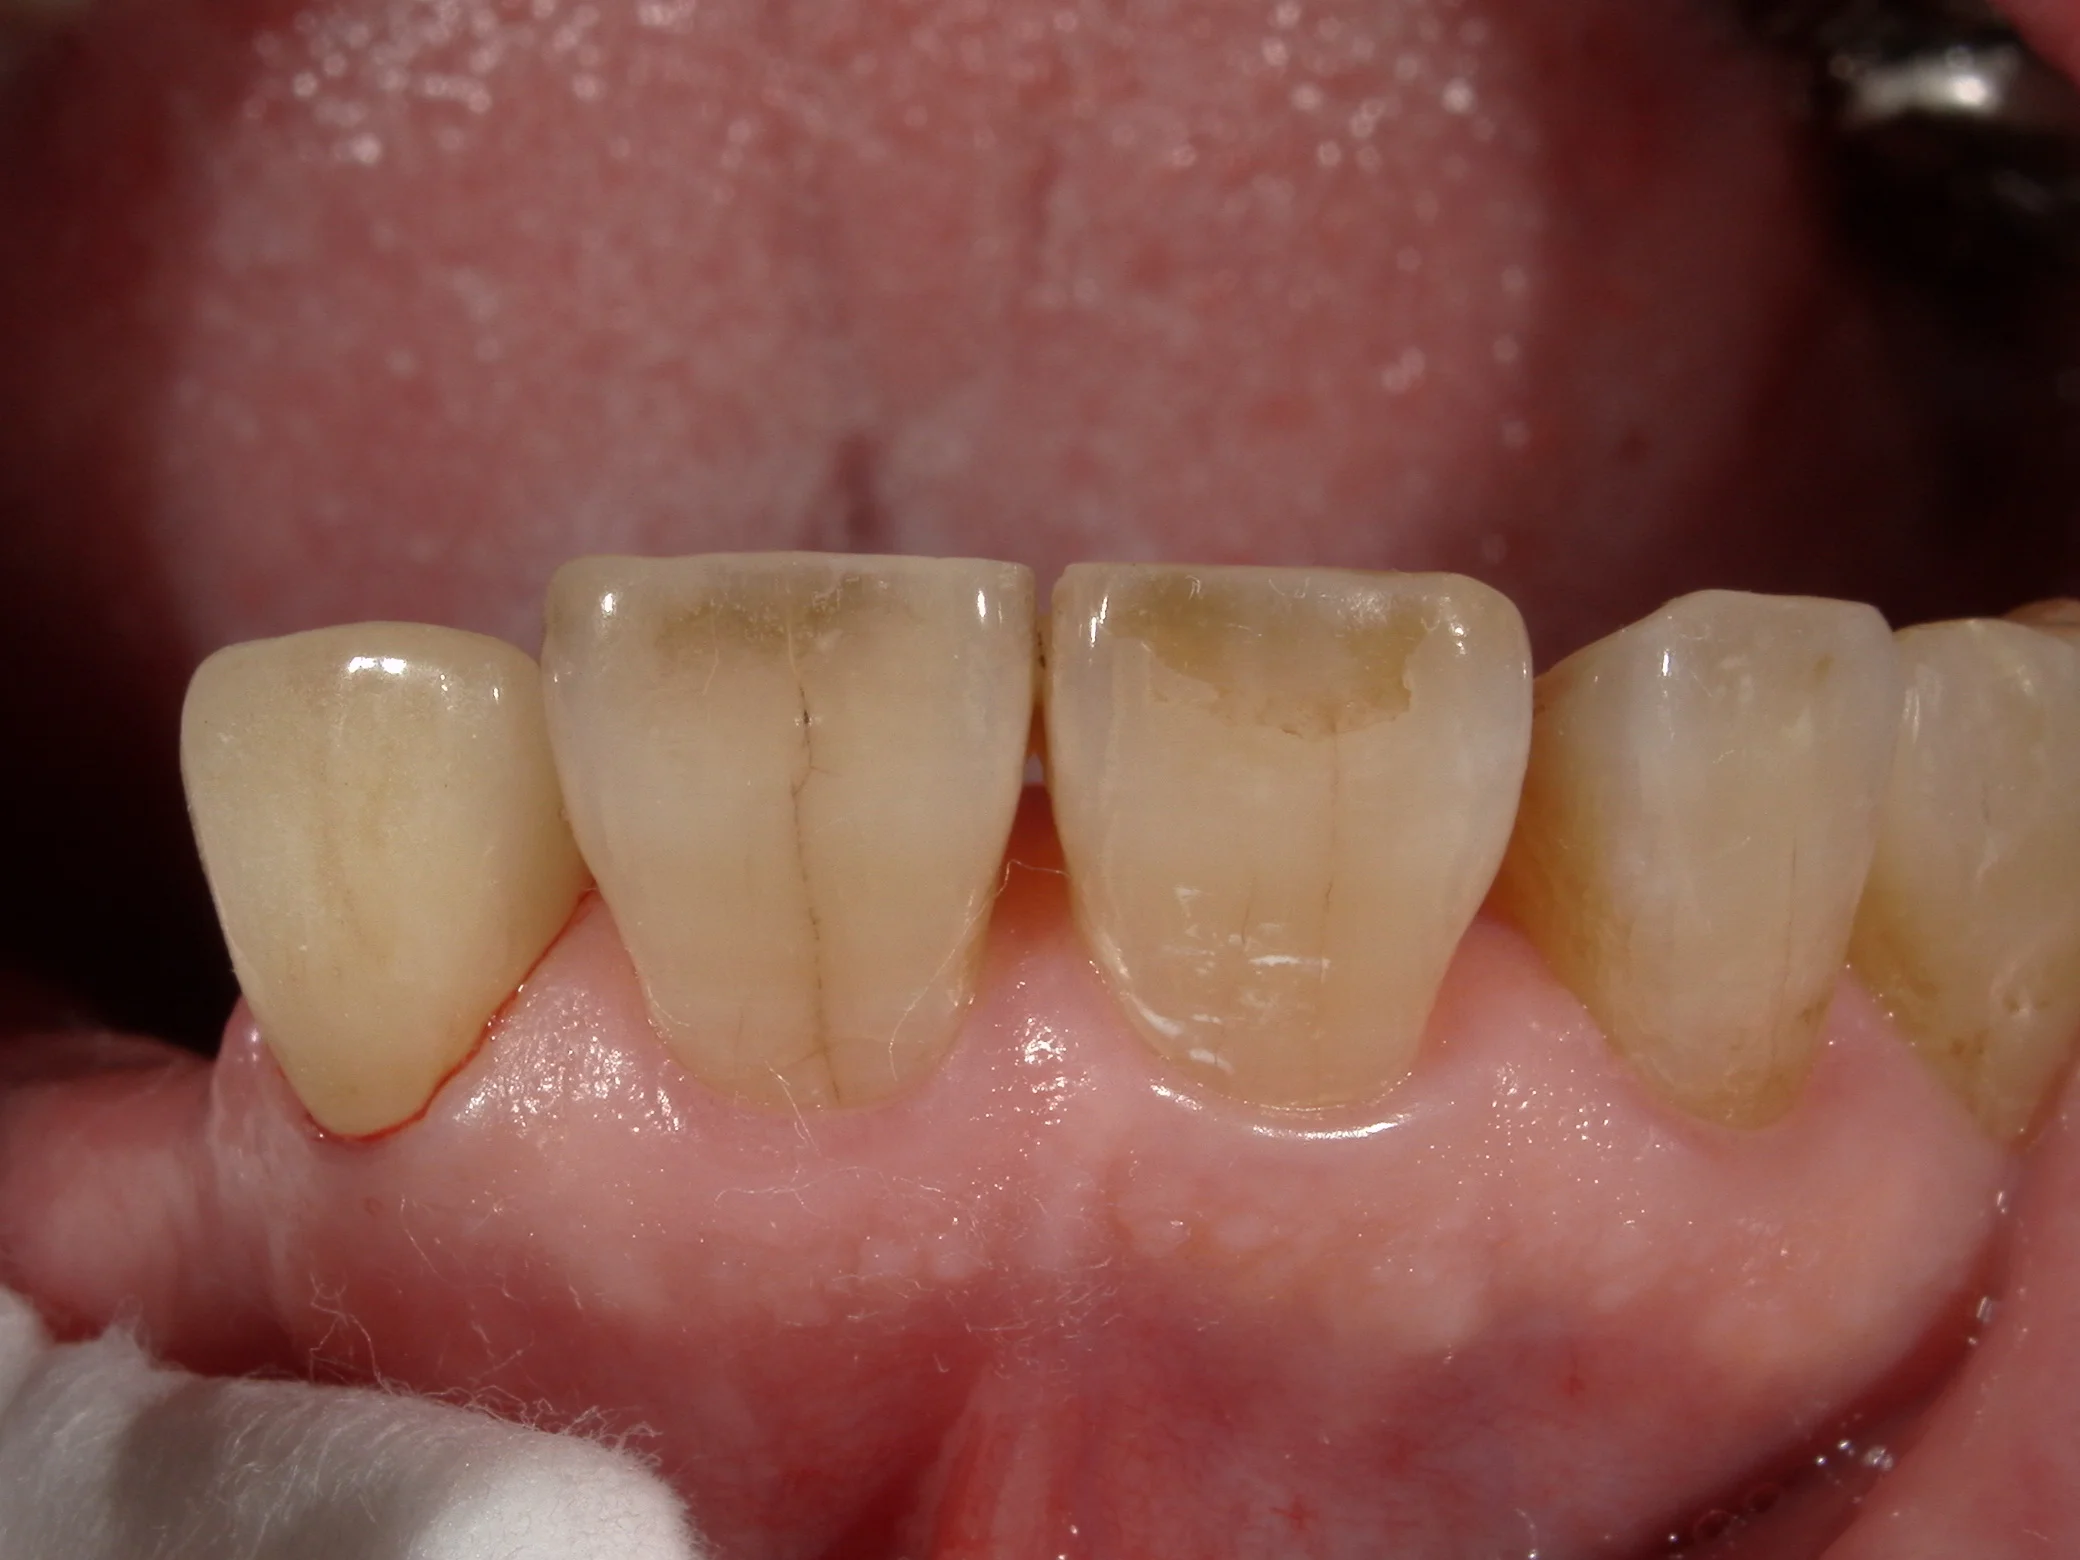

これをカメラの機能であるシェード抽出機能を用いて撮影するとこうなります。

セラミックでの色の再現度を上げるために・・・|坂寄歯科医院(取手市藤代) - 画像4

歯の色だけピックアップしてくれるので、前後の歯と色を合わせやすいんですね。